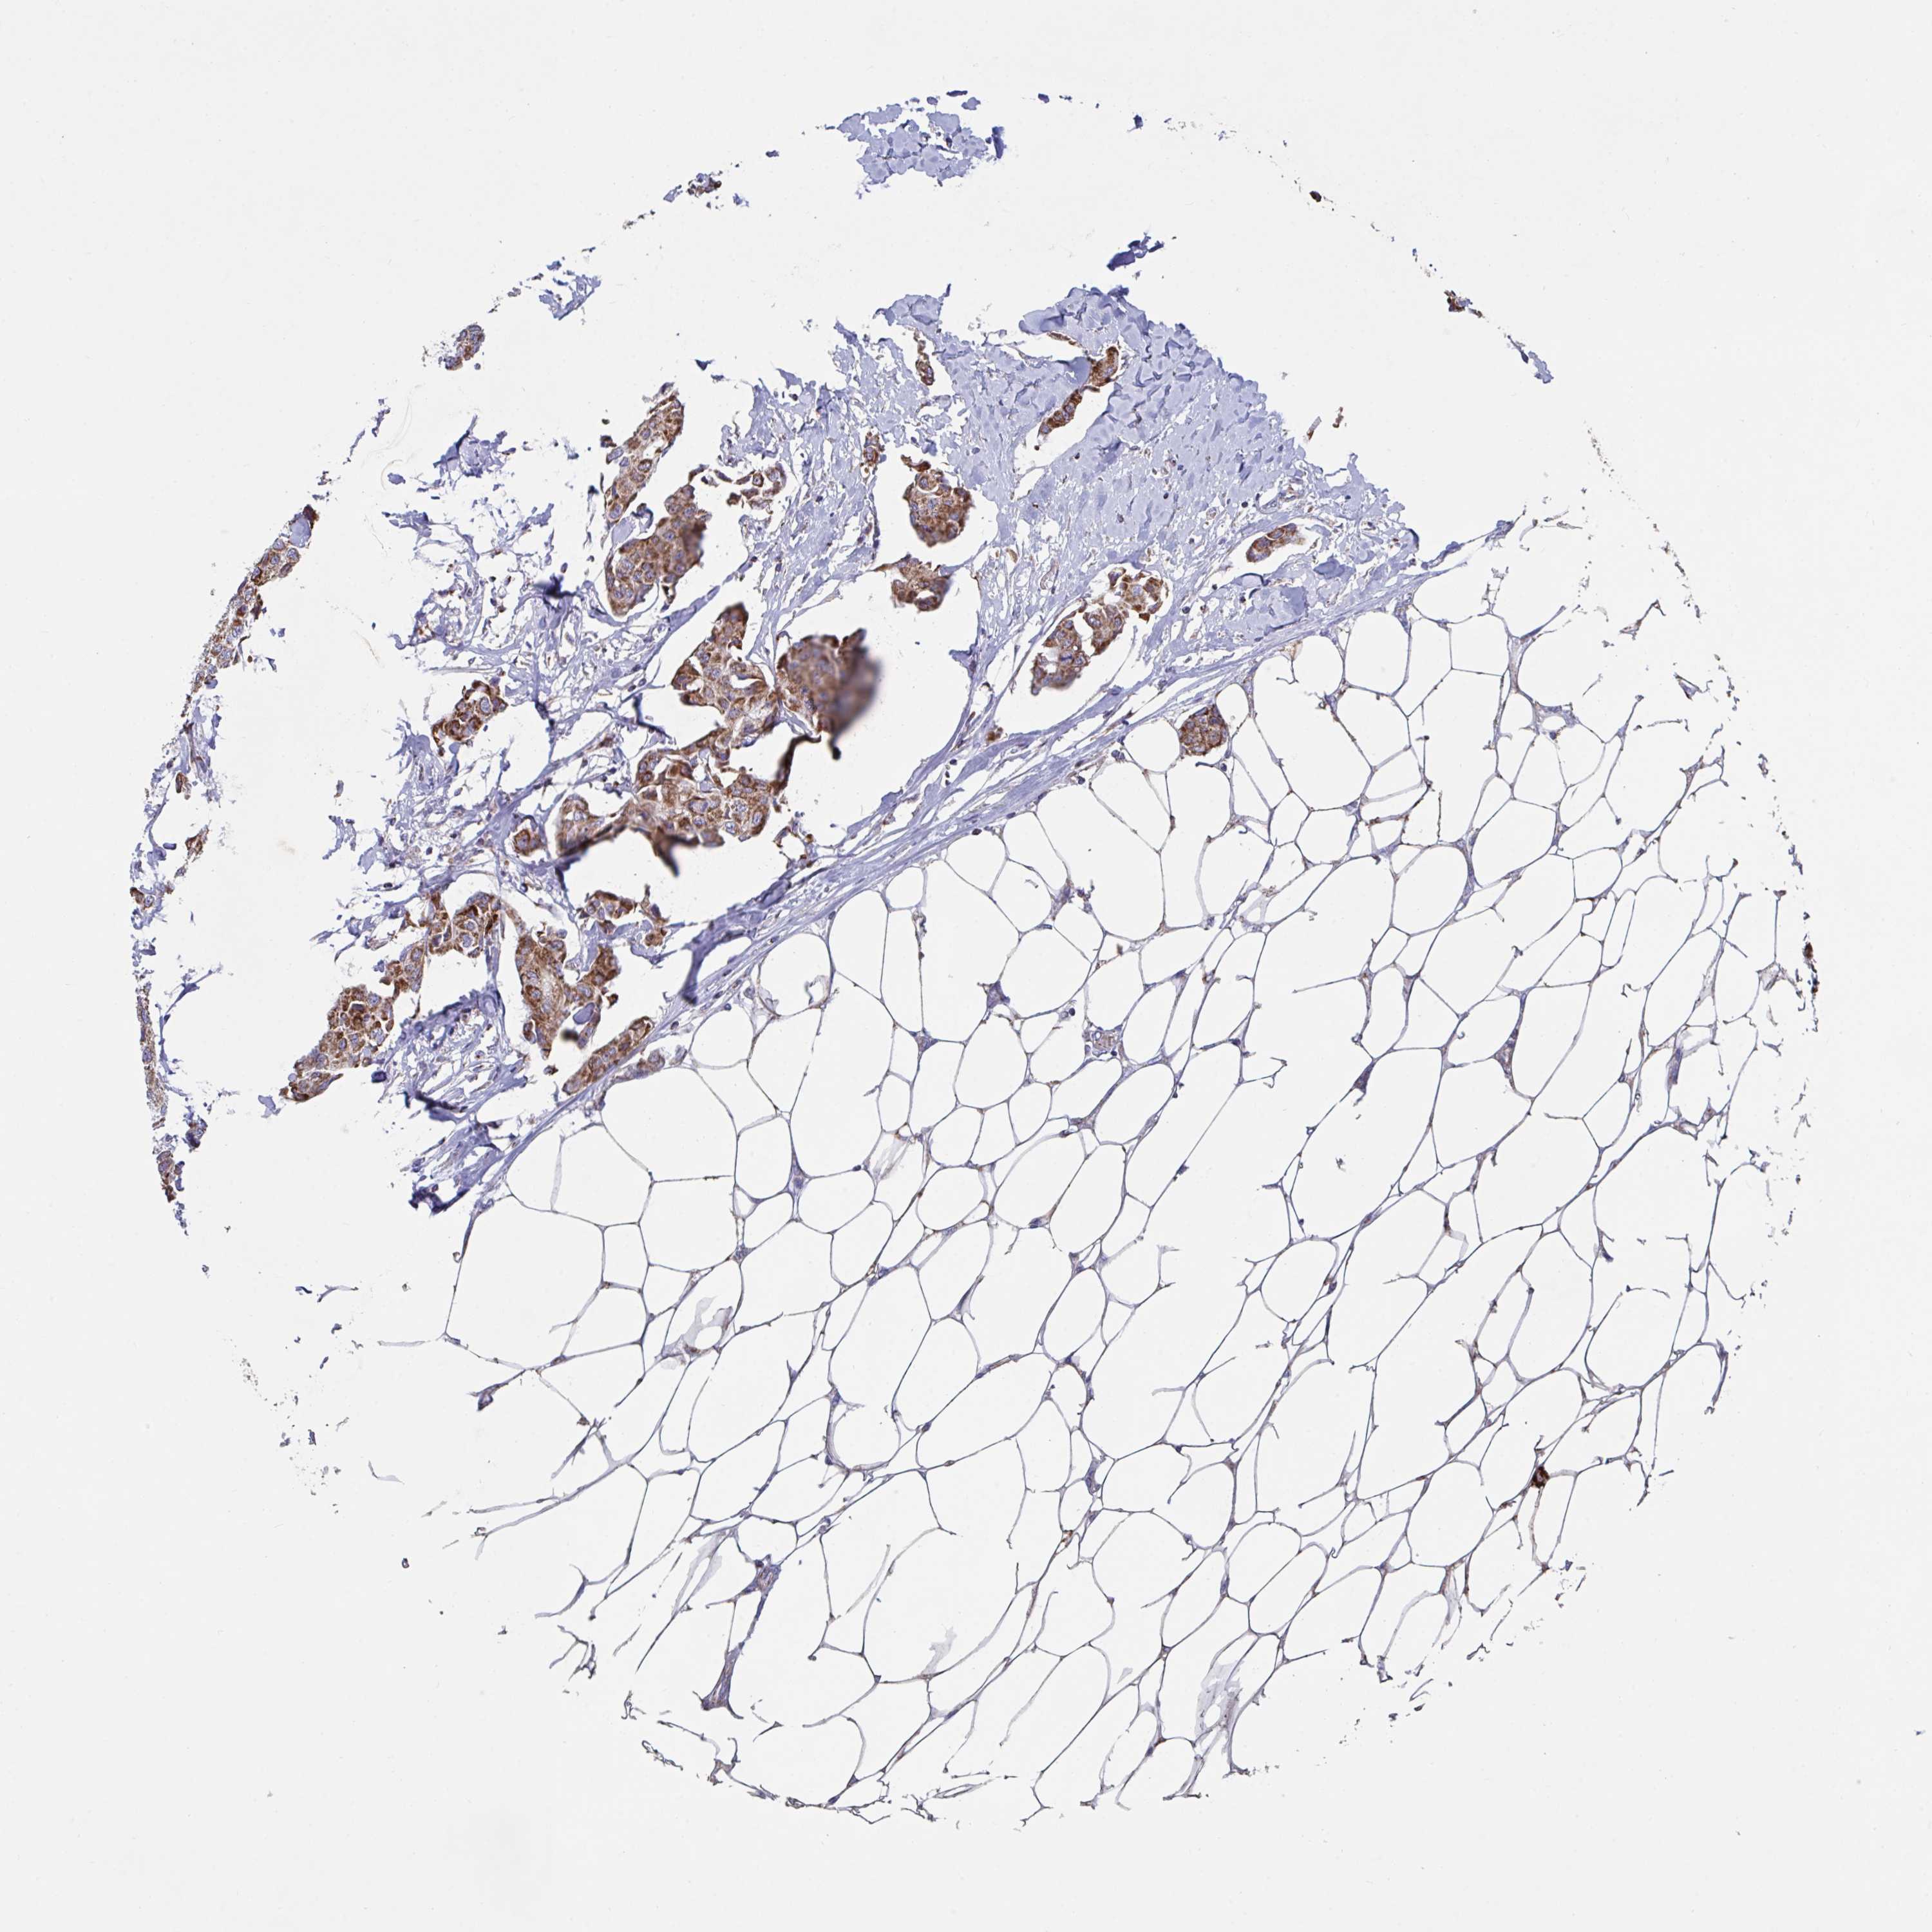

CANCER BREAST CANCER Show tissue menu

BRCA TCGA BRCA VALIDATION PROTEIN EXPRESSION